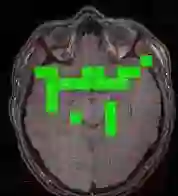

The use of deep learning techniques for 3D brain vessel image segmentation has not been as widespread as for the segmentation of other organs and tissues. This can be explained by two factors. First, deep learning techniques tend to show poor performances at the segmentation of relatively small objects compared to the size of the full image. Second, due to the complexity of vascular trees and the small size of vessels, it is challenging to obtain the amount of annotated training data typically needed by deep learning methods. To address these problems, we propose a novel annotation-efficient deep learning vessel segmentation framework. The framework avoids pixel-wise annotations, only requiring patch-level labels to discriminate between vessel and non-vessel 2D patches in the training set, in a setup similar to the CAPTCHAs used to differentiate humans from bots in web applications. The user-provided annotations are used for two tasks: 1) to automatically generate pixel-wise labels for vessels and background in each patch, which are used to train a segmentation network, and 2) to train a classifier network. The classifier network allows to generate additional weak patch labels, further reducing the annotation burden, and it acts as a noise filter for poor quality images. We use this framework for the segmentation of the cerebrovascular tree in Time-of-Flight angiography (TOF) and Susceptibility-Weighted Images (SWI). The results show that the framework achieves state-of-the-art accuracy, while reducing the annotation time by up to 80% with respect to learning-based segmentation methods using pixel-wise labels for training